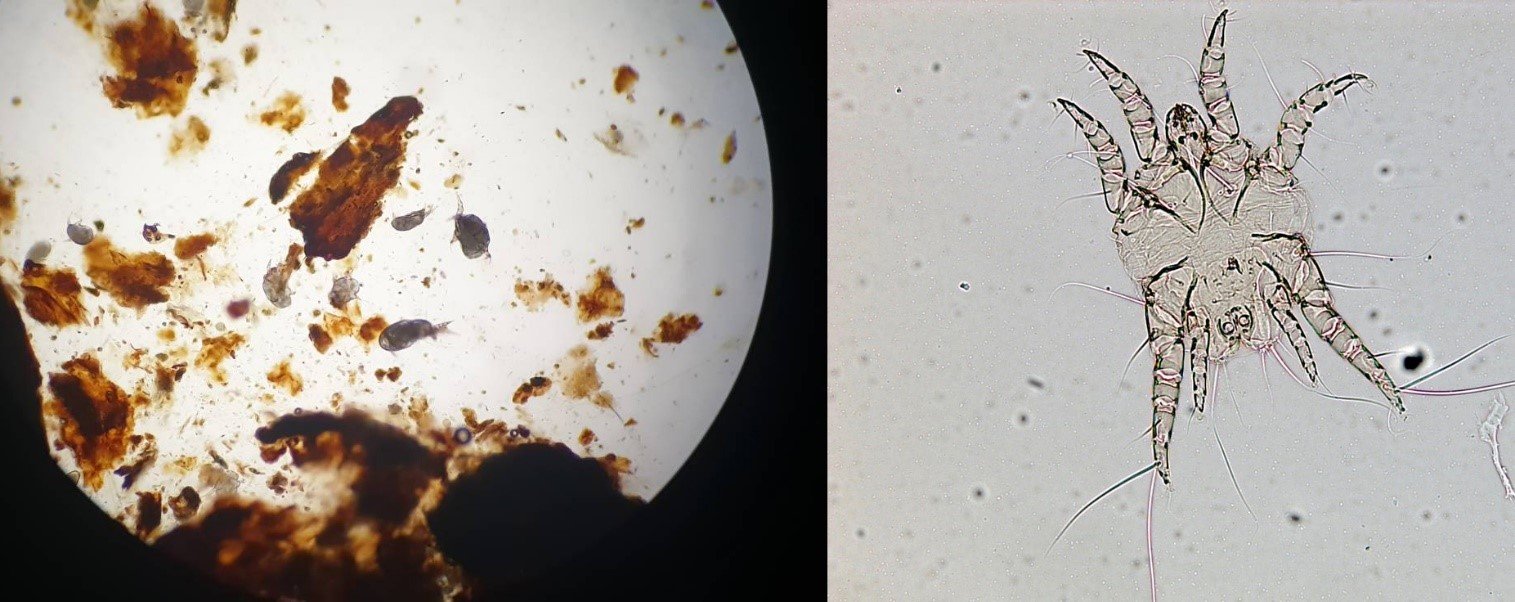

การตรวจวินิจฉัยโรคนี้ทำได้ไม่ยาก แม้เจ้าไรพวกนี้จะสามารถเห็นได้ด้วยตาเปล่าเป็นจุดเล็กๆสีขาวๆแต่ก็ยังถือว่ามีขนาดจิ๋วมากๆ ดังนั้นเพื่อวินิจฉัยยืนยันควรนำขี้หูของสัตว์เลี้ยงไปส่องดูด้วยกล้องจุลทรรศน์ หากติดเชื้อจริง ก็จะพบเจ้าตัวไรดิ้นดุ๊กดิ๊กอยู่เต็มไปหมดเลยค่ะ